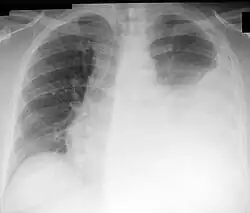

A: Flüssigkeitsspiegel

B: Grenze der rechten Lunge und der Pleurahöhle

Auf der beim Verdacht auf das Vorliegen eines Pleuraergusses empfohlenen Röntgenaufnahme des Brustkorbs sind Pleuraergüsse in der p.-a.-Thoraxaufnahme meist ab einem Volumen von 200–300 ml, bei der seitlichen Aufnahme ab 50 ml erkennbar.[2]:S. 380 Typisch ist bei einer im Stehen angefertigten Aufnahme eine nach lateral (außen) ansteigende Verschattung (dargestellt durch die den Erguss begrenzende Damoiseau-Ellis-Linie, auch Ellis-Damoiseausche Linie[5] genannt[6]).